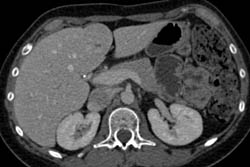

Focal Nodular Hyperplasia (FNH)